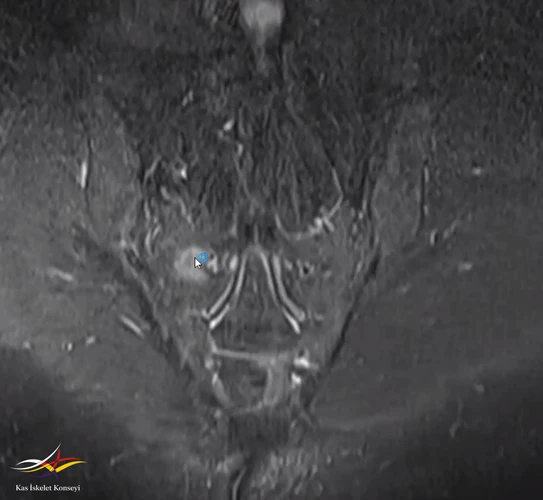

Resim 2. Sakroiliak MRG'de sakrum sağında intansite artışı (ekleme komşu olmayan bölgede).